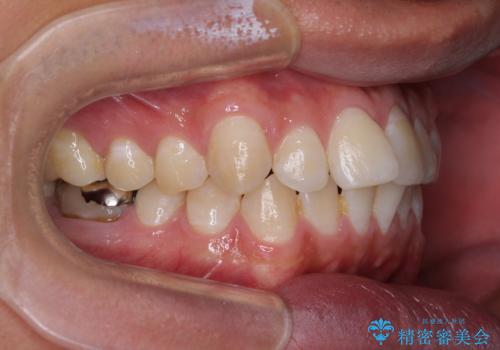

ワイヤー装置でもマウスピースでも対応可能でしたが、自己管理の煩わしさを気にされ、ワイヤー装置にて矯正治療を行うこととしました。

矯正治療後は、奥歯の銀歯をセラミッククラウンにて補綴治療を行うこととしました。

あっという間に歯列が整い、目立っていた銀歯もなくなり、清潔感のある口元になりました。